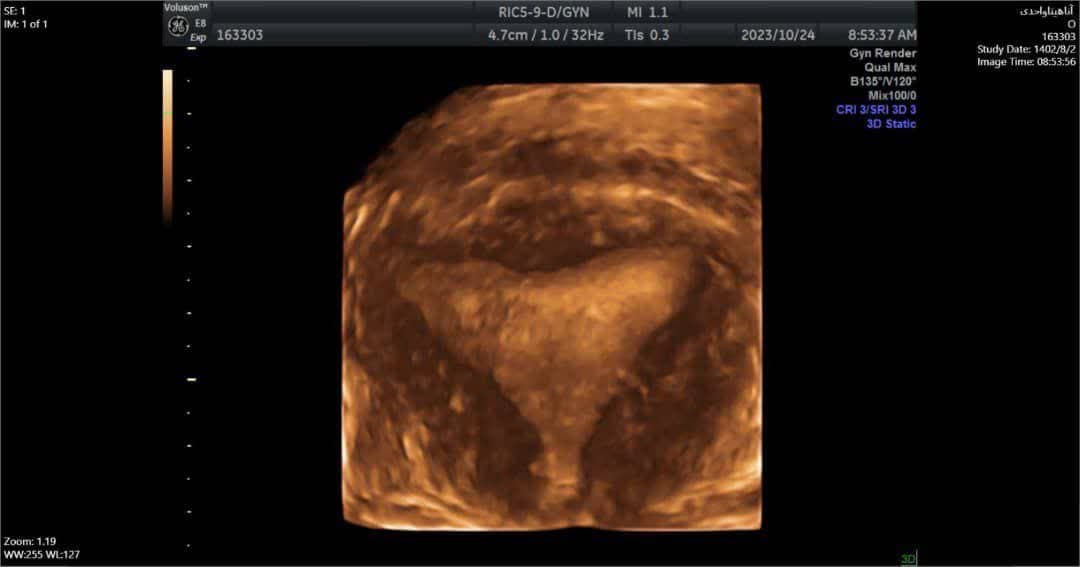

-انجام سونوگرافی سه بعدی: بعد دیگری به تصویر اولتراسوند سونوگرافی فرد اضافه می کند و به جای تصاویر دو بعدی تخت ساخته شده با سونوگرافی سنتی، تفاسیر سه بعدی ایجاد می کند.